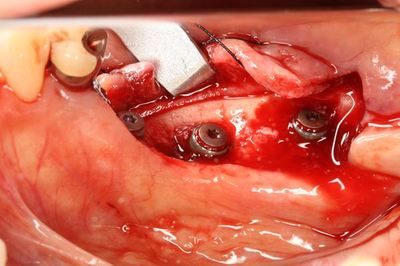

皮質骨にあえて穴をあけて出血を促したところです(デコルチケーション)。

この状態にさらに上の写真の骨切削片を盛り足して縫合します。

多めに盛っておくことが重要です。